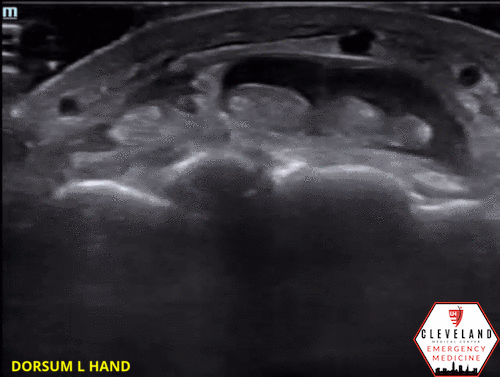

Longitudinal view of the 3rd extensor tendon again demonstrating fluid above and below. 2nd & 4th tendons had similar appearance.

POCUS findings: fluid in the tendon sheath surrounding the extensor tendons along with thickening and mild cobblestoning of the overlying soft tissues. No abscess visualized. Findings suggestive of extensor tenosynovitis.